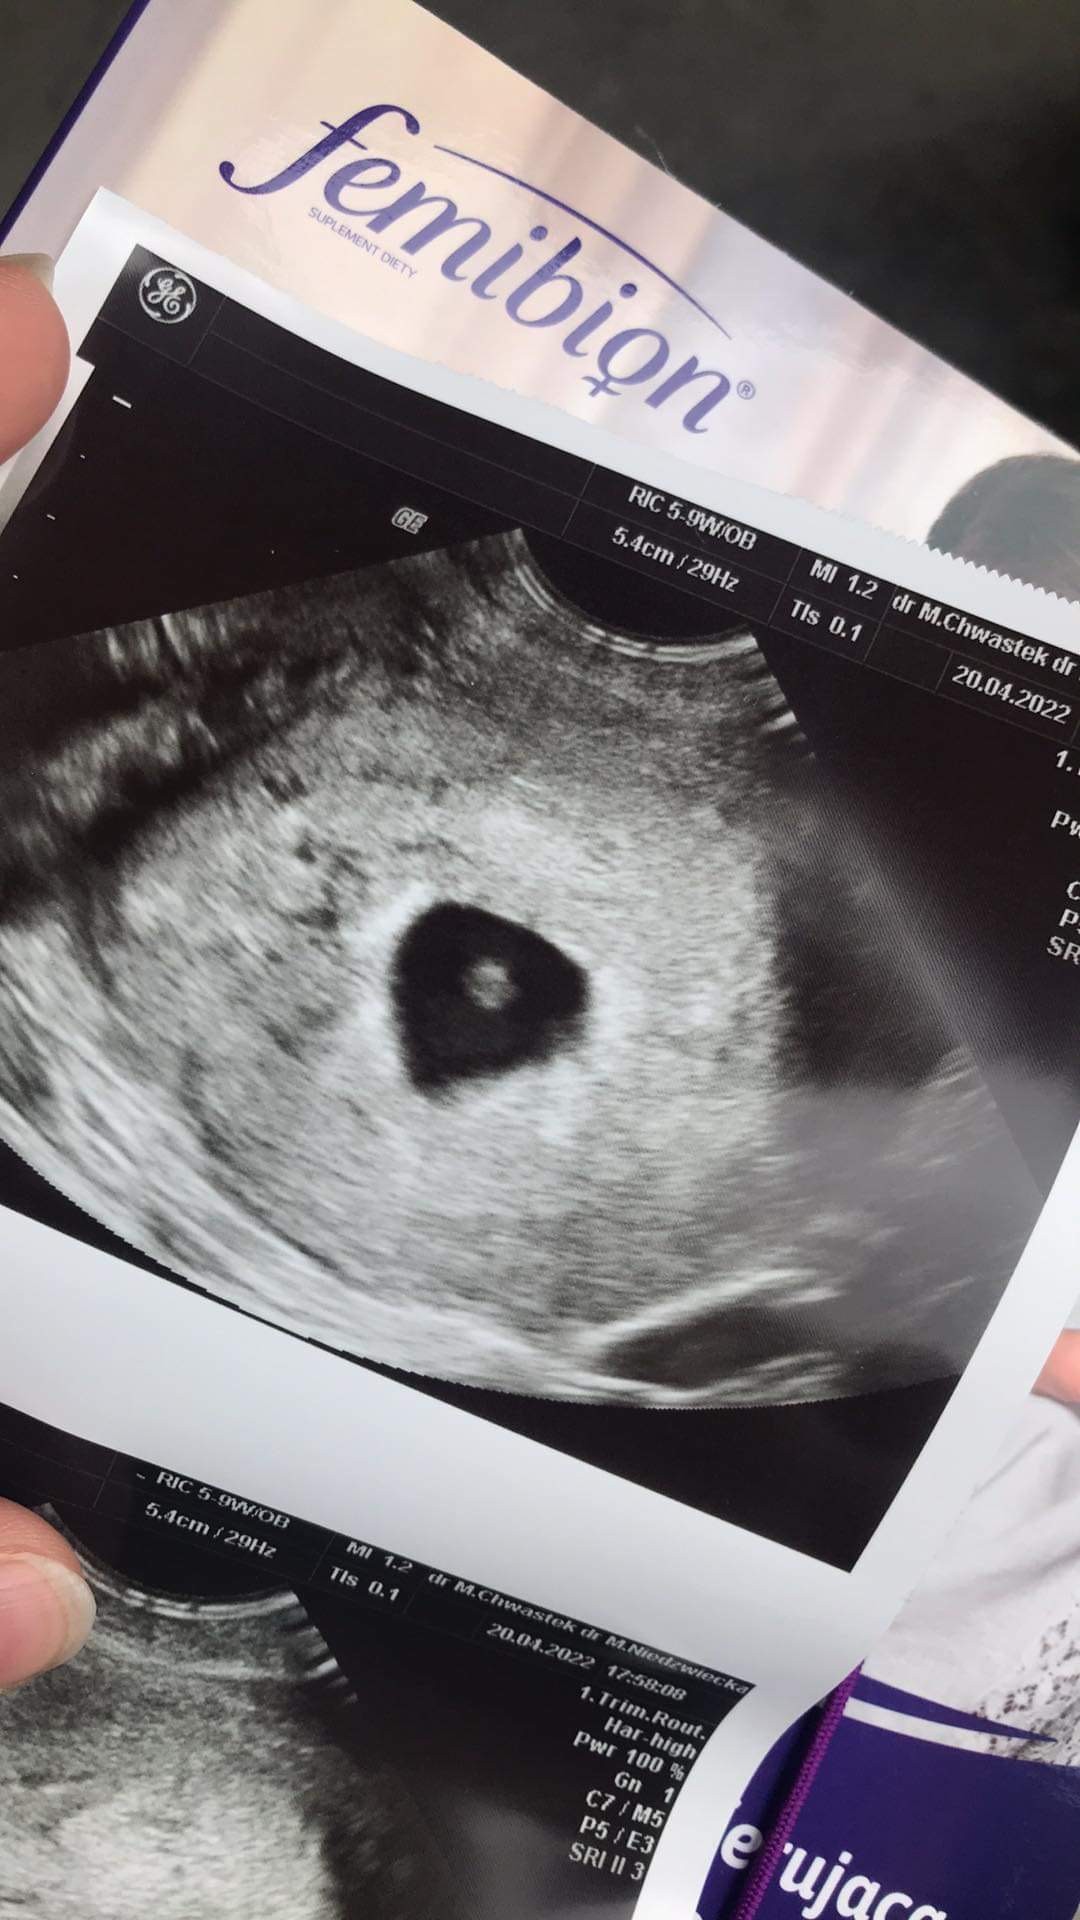

wybacz, dopiero ochłonęłam. 5+5 jest wzorowo. Pęcherzyk i ciałko żółte adekwatne do wieku ciazy i zgodne z OM. Z progiem dostałam luteinę profilaktycznie dopochwowo, ale lekarz moi, ze jest na tyle wzorowo, ze nerwy mam schować w kieszeń i odetchnąć. Za dwa tyg wizyta kolejna. Mam wrócić z badaniami zleconymi. ❤️❤️❤️ gdybym przyszła w poniedziałek na 99% byłoby juz serduszko, ale byłam dziś i wyszłam spokojniejsza. Serduszka nie było, ale był najpiękniejszy kropek na świecie. ❤️

• 8B74B302-29F8-47D3-B688-3B8FE22629A3.jpeg

214,1 KB · Wyświetleń: 87